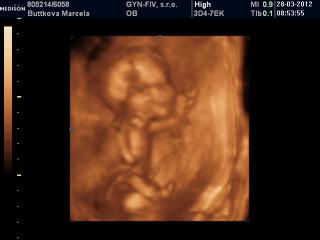

@tominka...ja som bola na 3D/4D pri malom v 23tt...pozri na foto co mam v albume, podla mna velmi pekne.

@tomika kvalita závisí od prístroja ktorý doki používa. Ja som bola na 3/4D v 16tt (viď foto) a idem ešte v 26tt. Ale čím skôr ideš tým viac sa bábo podobá na mimozemšťana 😀 😀 😀 možno preto ti vravela, že je lepšie ísť v 24-28tt. Keď je to ešte neskôr, bábätko už má málo miestečka a to tiež nie je veľmi dobre vidno vtedy. Ale zasa ak vám to vychádza najlepšie na budúci týždeň, myslím, že lepšie skôr ako nikdy 🙂

@marcelatje dakujem,a krástne vidno aj v 16tt,kvelitné fotky.No,nás objednal na 4.5.Dufam že volačo uvidime 🙂 .Predchádzajucich tehu sme neboli na 3D.Tak teraz pojdeme.Ibaže mm teraz robi v zahraniči,a nevieme kedy nabuduce pride domov..Teraz je doma,tak teraz pojdeme 😉 .